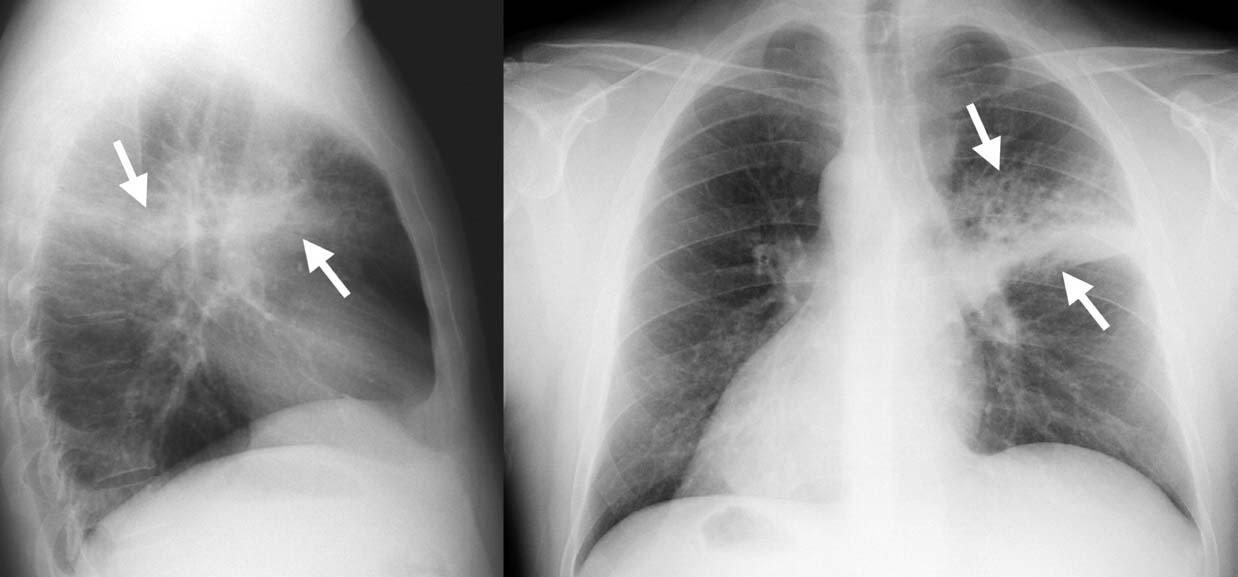

Основную роль в постановке окончательного диагноза отводят рентгену грудной клетки.

Пневмония на рентгеновском снимке

На снимках, полученных после рентгенологического исследования, отмечается усиленный сосудистый рисунок, участки потемнения легочной ткани и рассеянная перибронхиальная инфильтрация.

Если у врачей имеются сомнения в диагнозе, то они назначают малышу обследование сердца, которое исключит или подтвердит наличие предрасполагающих к воспалению легких факторов.